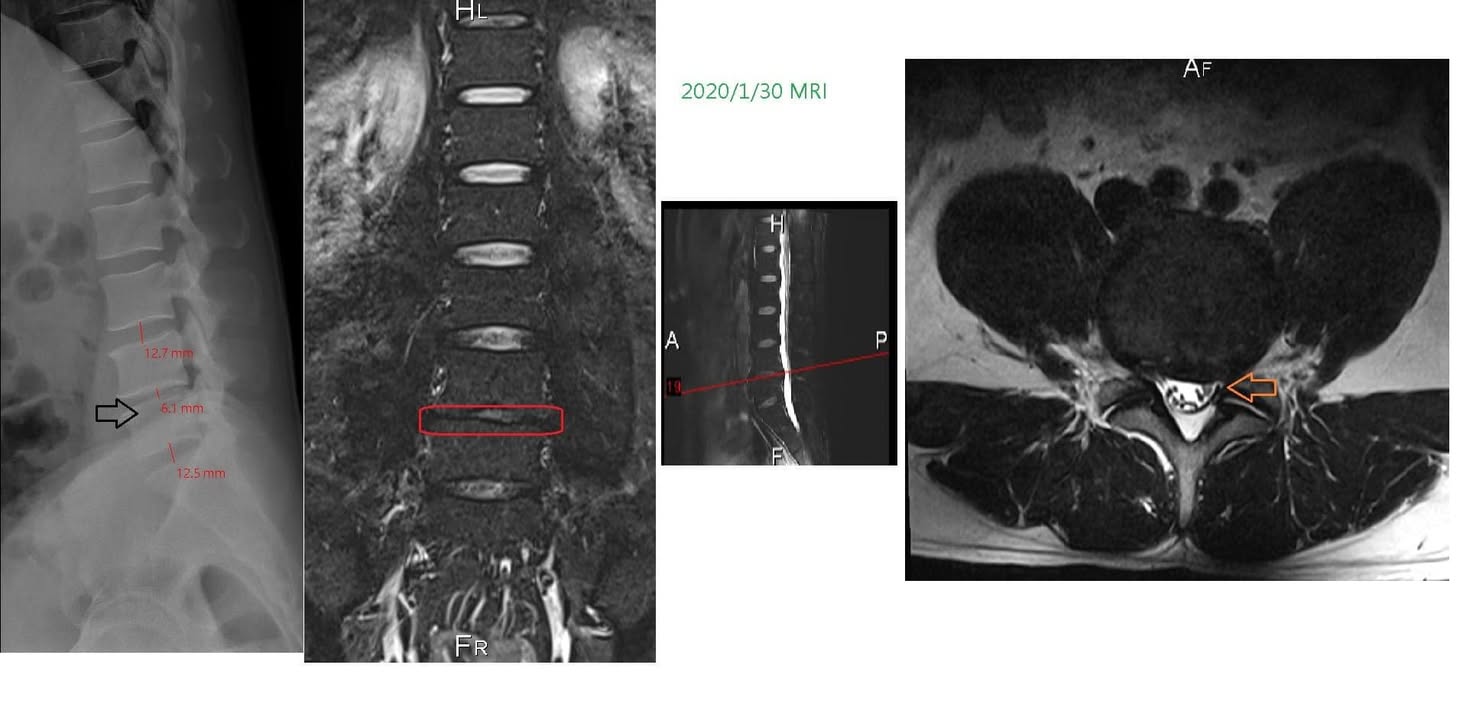

Cervical Spine Treatment Cases 腰椎治療案例 史上超多內心小劇情醫案文章請耐心看完 辛苦的貨車司機腰椎辛酸血淚史 各式各樣治療都... 2020.04.24 感謝台中后里區鍾小姐熱情見證 車禍後導致椎間盤突出 痛到懷疑人生原本考慮開刀治療 ... 2020.04.16 #腰椎滑脫合併椎管狹窄醫案 #脊椎整合中醫微創逆轉勝 #老人家不可以跌倒不可以跌到 #... 2020.04.11 #搬重物閃到腰受傷一痛就痛兩年 #復健許久沒效拍攝核磁共振才知道椎間盤突出 #脊椎整... 2020.04.10 #抱狗閃到腰居然痛麻到不行快半年 #原來是椎間盤突出啊 #脊椎整合中醫微創逆轉勝 2020.04.03 #腰椎滑脫逆轉勝醫案 #曾經大痛到一個月無法走路居家臥床 #原本認真考慮接受骨科融合... 2020.03.31 #腰椎輕微滑脫醫案 #感謝桃園八德蔡阿姨熱情見證 #脊椎整合中醫微創 2020.03.20 腰痛到小腿一直麻痛是怎麼回事 腰椎第四第五椎間盤突出惹禍 打噴嚏跟咳嗽都超痛的 脊... 2020.03.11 #腰椎明顯滑脫醫案 #感謝三重蔡先生熱情見證 #曾經大痛到無法工作跟無法睡覺 #脊椎整... 2020.03.07 #感謝雲林李阿姨熱情見證 #腰椎滑脫合併椎管狹窄 #脊椎整合中醫微創療法逆轉勝 2020.03.01 曾經腰痛連大腿小腿到無法睡覺 大醫院核磁共振檢查後證實椎間盤突出 四個多月的疼痛原... 2020.03.05 #跨國治療台灣醫療奇蹟 #遠從澳洲坐飛機回台專門接受治療 #台灣中醫脊椎整合微創療法... 2020.01.17 #兒子老婆陪同林伯伯一起見證奇蹟 #腰椎滑脫合併椎管狹窄 #治療前走路無法超過五分鐘 ... 2019.12.28 #跨國治療台灣醫療奇蹟 #遠從越南坐飛機專門接受治療 #台灣中醫脊椎整合微創療法立大... 2019.12.26 再度逆轉勝!腰椎治療醫案 原本痛到懷疑人生都想去手術了 八週治療後生路活虎!還可以... 2019.12.18 ← 上一頁 11 12 13 14 15 下一頁 →